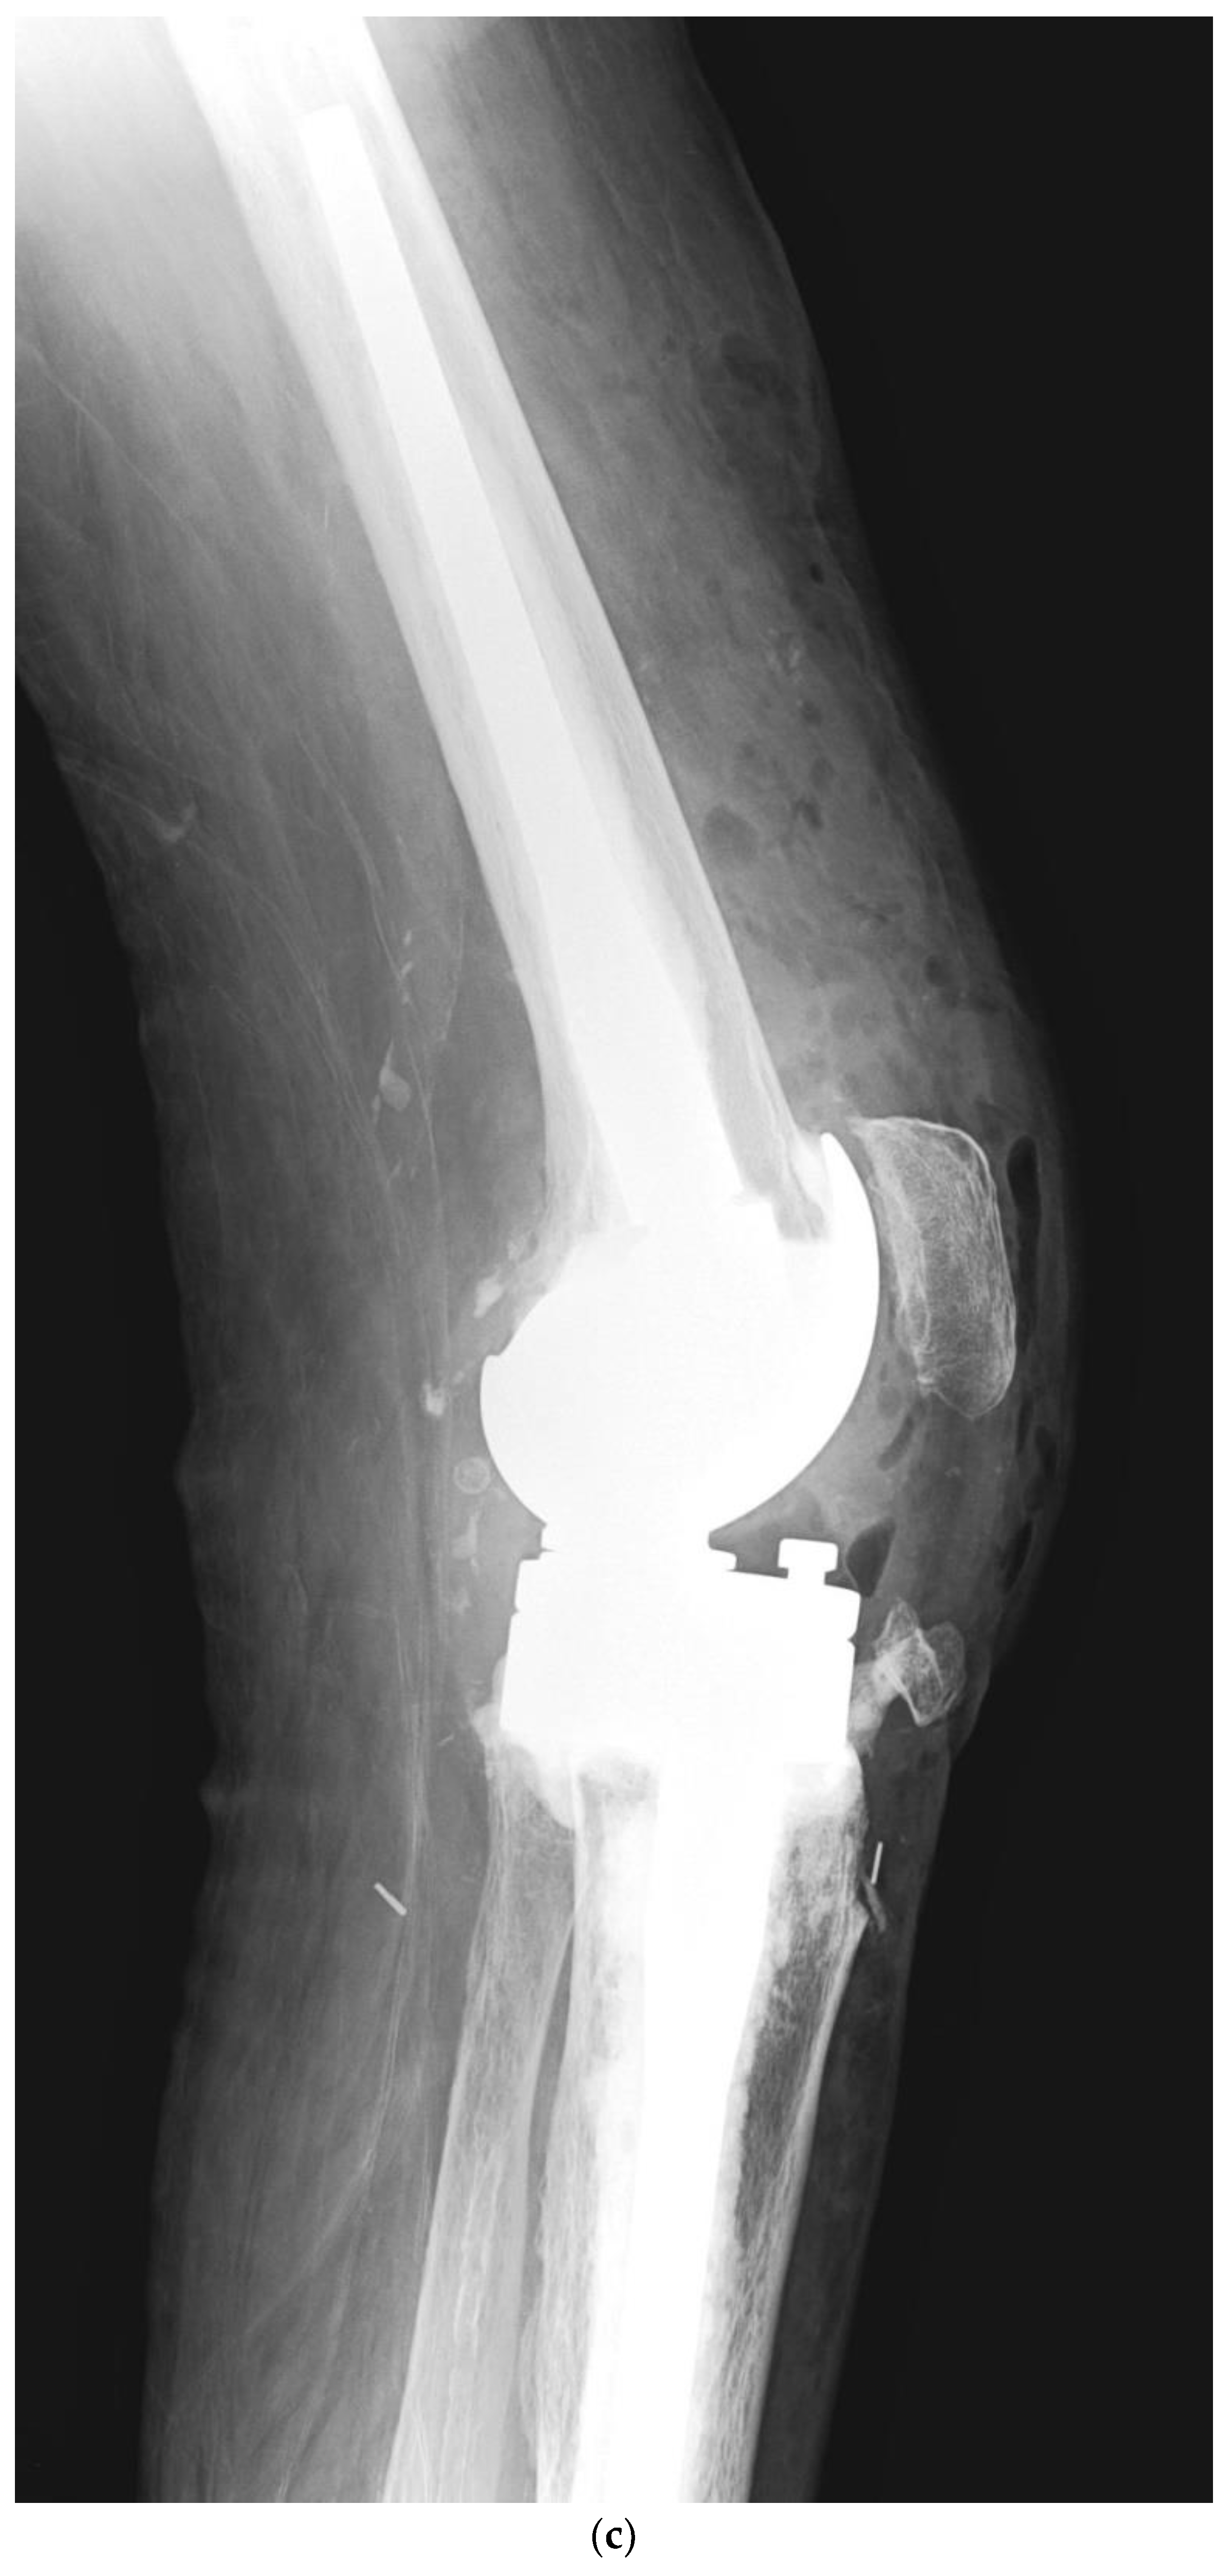

Risk Factors for Periprosthetic Joint Infection after Primary Total Knee Arthroplasty